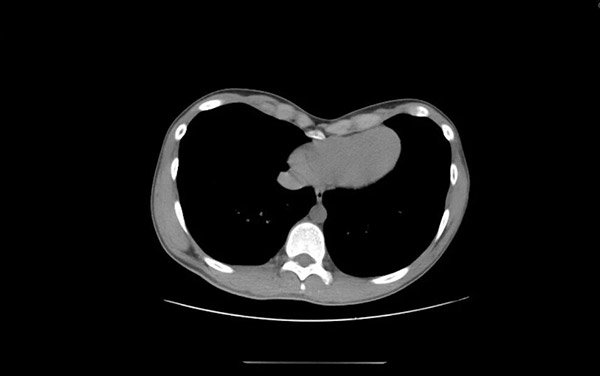

手术前